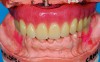

Fig 1. The face collapses inward when the bone and teeth are lost.

Figure 1

Often when teeth are lost as a result of periodontal disease, tooth decay, or traumatic injury, alveolar bone that houses teeth is lost. Particularly in the maxillary arch, bone loss moves the bony scaffolding supporting the facial muscles medially, posteriorly, and superiorly, causing loss of lip support and eversion. Figure 1 and Figure 2 illustrate the inward collapse of the face when the bone and teeth are lost.